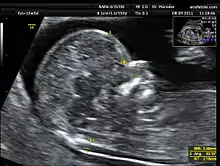

سونوگرافی ان تی (به انگلیسی: Nuchal scan یا nuchal translucency) یک روش تصویربرداری و بخشی از غربالگری سه ماه اول بارداری است که از آن برای تشخیص ناهنجاریهای احتمالی کروموزومی در جنین استفاده میشود.[1] از آنجایی که ناهنجاریهای کروموزومی میتواند منجر به اختلال در رشد قلب و عروق نوزاد شود، از سونوگرافی ان تی به عنوان روش غربالگری برای بیماریهایی مانند سندرم داون، سندرم پاتو، سندرم ادواردز استفاده میشود.[2]

در این سونوگرافی تشخیصی از اندازهگیری دو مارکر به نام استخوان بینی (nb) و ضخامت مایع پشت گردن جنین (nt) استفاده میشود. اندازهگیری ضخامت مایع پشت گردن جنین بهطور معمول در پایان سهماهه اول، بین هفته ۱۱ تا ۱۳ بارداری و همچنین در سهماهه دوم بارداری انجام میشود.[3] با افزایش ضخامت مایع، احتمال ناهنجاری و مرگ و میر کروموزومی افزایش مییابد. از طرفی این سونوگرافی به انتخاب تاریخ دقیق تر برای زایمان و تشخیص سلامت جنین نیز کمک میکند.[4]

این سونوگرافی از یازده هفته و صفر روز تا سیزده هفته و شش روز قابل انجام است و بهترین زمان انجام هفته دوازدهم بارداری است. در این سونو تصویر جنین تا ۷۵٪ بزرگتر شده و روی صفحه متصل به دستگاه، نمایش داده میشود. سپس با دقت باید اندازهگیریهای گفته شده از روی تصویر انجام گیرد.

ضخامت مایع پشت گردن جنین به طول فرق سر تا دنبالچه (CRL) جنین بستگی دارد. متأسفانه در میان آن دسته از جنینهایی که میزان این ضخامت بیش از مقادیر طبیعی است، احتمال بروز ناهنجاری قابل توجه، نسبتاً زیاد است.[5]

مقادیر بدست آمده هنگامی که CRL بین ۴۵ تا ۸۴ میلیمتر است (۱۱ هفته ۳ روز تا ۱۳ هفته ۶ روز) ممکن است برای غربالگری ترکیبی سهماهه اول استفاده شود. ضخامت کمتر از ۲٫۲ الی ۲٫۸ میلیمتر با افزایش خطر همراه نیست، اما این موضوع تا حدی نیز به سن مادر بستگی دارد و باید با سن دقیق بارداری و CRL مطابقت داشته باشد. در موارد ضخامت بالاتر از ۳ میلیمتر باید تستهای تکمیلی مانند آمنیوسنتز یا سل فری انجام شود.[6]